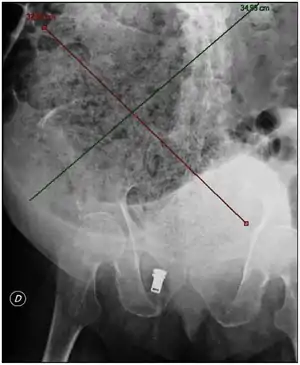

| Plain abdominal X-ray showing a huge fecal impaction extending from the pelvis upwards to the left subphrenic space and from the left towards the right flank, measuring over 40 cm in length and 33 cm in width. | |